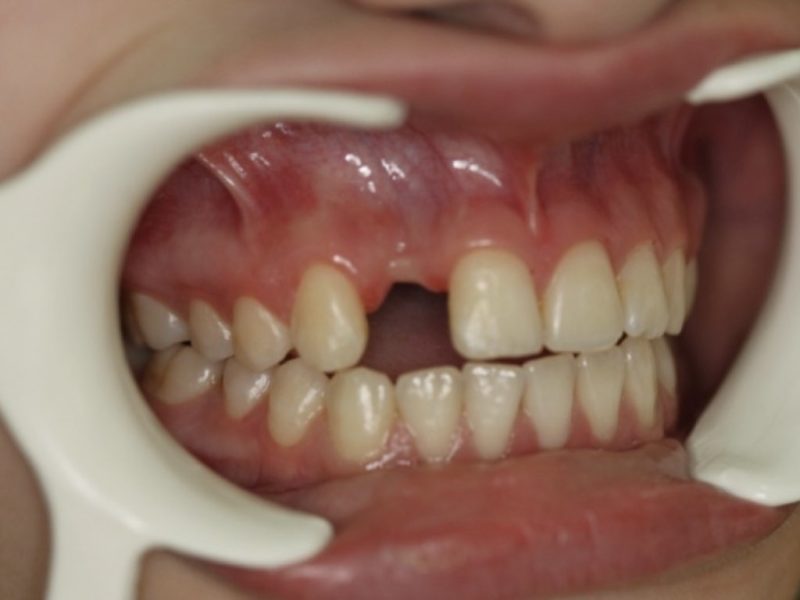

The patient came to our attention with the specific request to restore the aesthetic of her smile ruined by the missing of element 12. Therefore to perform the replacement of the anterior tooth we had to take in great consideration the highly aesthetical area and her very young age. We evaluater 3 treatment options: provide the patient with a partial denture, but due to her very young age did not seem the best way to pursue or prepare a fixed bridge,(3 units ,cantilever and/or Maryland) or insert an implant to provide her a comfortable solution to restore her self-confidence.

As the patient’s preference has been the insertion of an implant we plannes a two-stage delayed loading protocol treatment plan that involved guided bone regeneration (GBR) bone graft plus restorable membrane and the insertion of a Dura-vit B&B tapered dental implant-Ø 3.5, L 14mm.